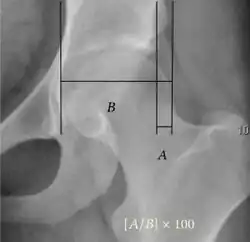

- Reimer's migration index (MI), also called the femoral extrusion index,[3] is calculated if hip dysplasia is detected. It can be used to indicate hip dislocation. It is the horizontal distance (parallel to the Hilgenreiner Line) between the Perkin line and the lateral border of the ossification center of the femoral head, divided by the horizontal width of the ossification center. The migration index is normally less than 33% by most sources,[9] but 25% and 30% has also been suggested.[10]

| Acetabular depth ratio |

Deepness of acetabulum. | >250

| Reimer's migration index[9] |

The percentage of the femoral head that lies outside of the acetabular roof. It is also called the femoral extrusion index. | <25% |